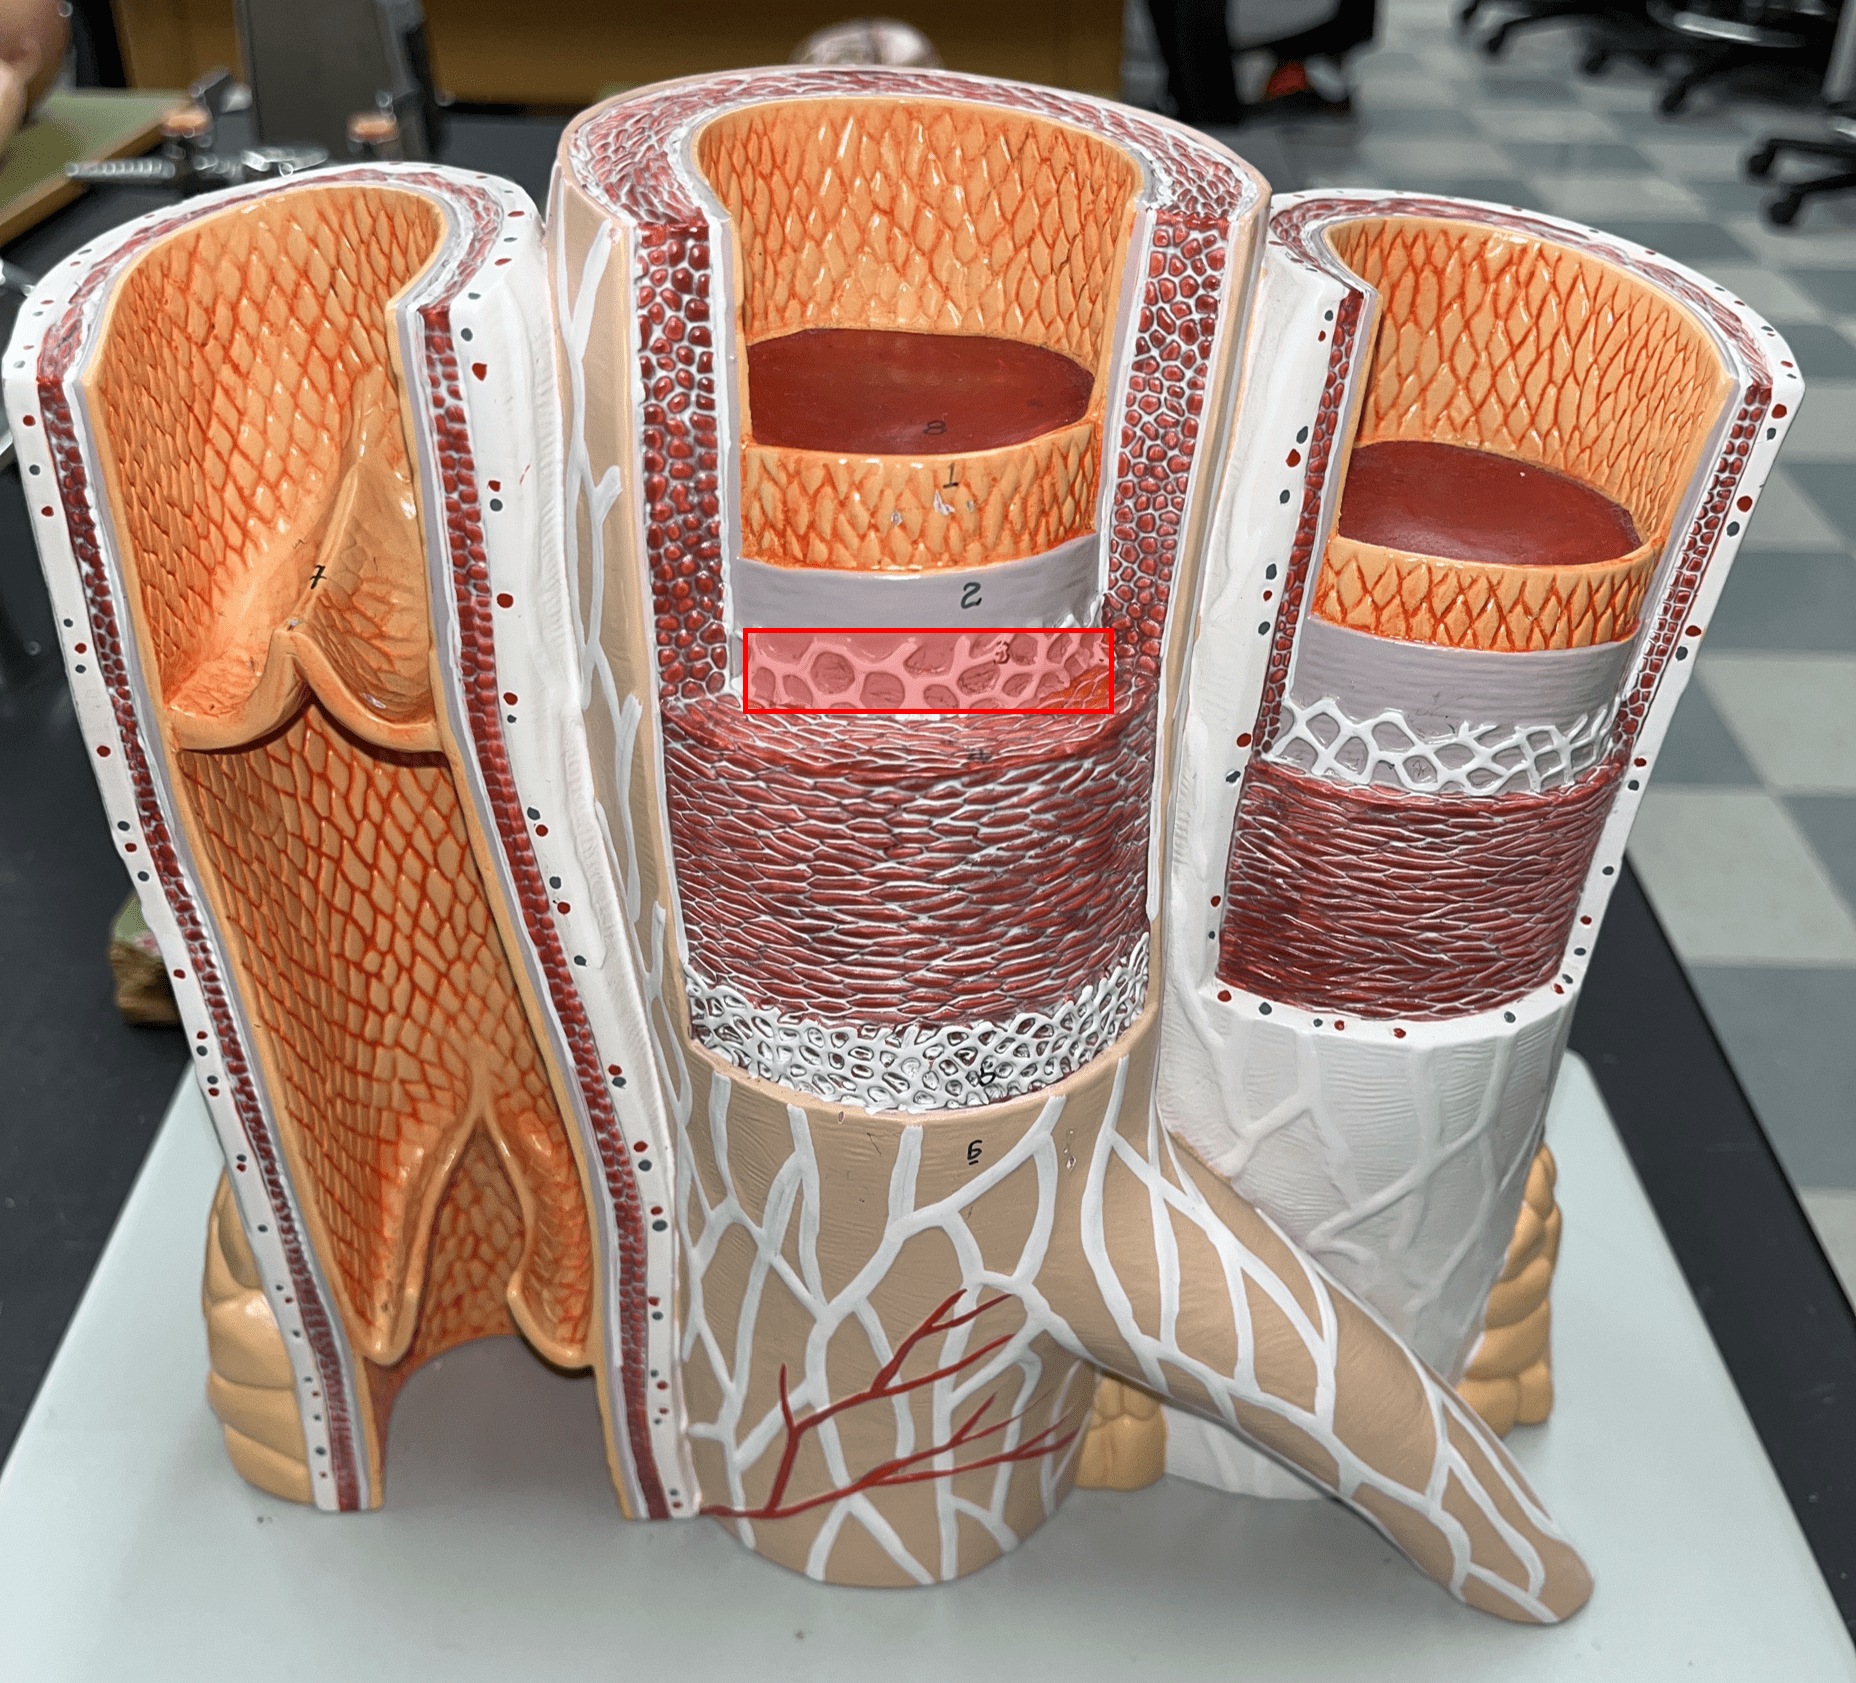

8

New cards

tunica media